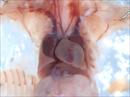

Caption: 1298-004-NA exhibits interrupted aortic arch (details)

Represented Alleles:

b2b1298Clo, Mutant line 1298; Bench to Bassinet Program (B2B/CVDC), mutation 1298 Cecilia Lo

Copyright: This image is from the Laboratory of Dr. Cecilia Lo, a member of the Cardiovascular Development Consortium (CvDC), Bench to Bassinet (B2B) program of the National Heart Lung and Blood Institute (NHLBI), and is displayed with the permission of the authors. J:175213